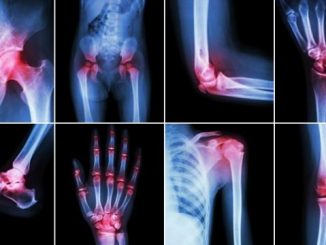

bol u zglobovima

Otečeni i bolni zglobovi na nogama i rukama uzroci i lečenje

May 17, 2020 simptomibolesti 0

Otoci ruku, nogu ili drugih organa najčešće su simptom neke hronične, uznapredovale bolesti. Do otoka dolazi kada je pritisak u krvnim sudovima i kapilarima toliki […]